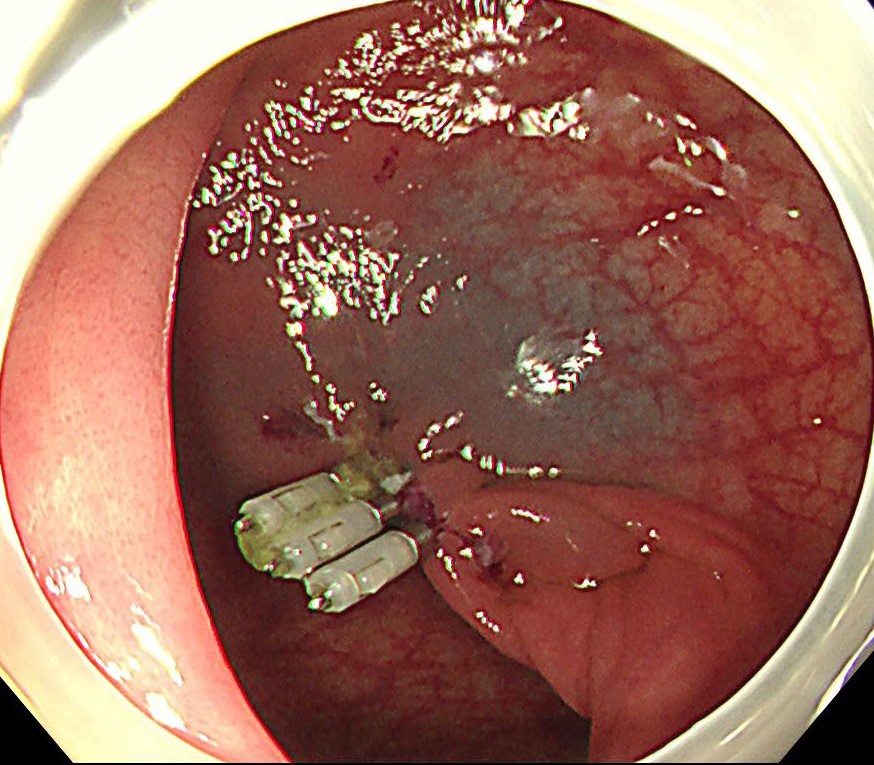

中年女性、下血にて来院。大腸内視鏡をしますと、直腸に15mm大のポリープを認めます。NBI(狭帯域光観察)では構造異形は乏しく、良性ポリープと診断しましたが、下血原因と考え、型のごとく内視鏡切除(EMR)しました。